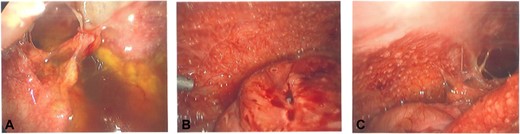

She had an urgent diagnostic laparoscopy by the general surgical team, which showed a physiological left ovarian cyst, a number of peritoneal and omental nodules (which were biopsied) and reactive serous fluid with extensive adhesions (Fig. 2A–C). The histology showed granulomatous inflammation; however, the DNA specific for Mycobacterium tuberculosis complex was not detected. She was reviewed by the infectious diseases team who diagnosed her with intra-abdominal TB based on the clinical history, histopathology, and she responded well to anti-TB medications.

(A–C) intra-operative photos demonstrating reactive ascites, yellow peritoneal nodules, and thickened bowel loops.

In another study, Bevin et al. (2018) performed a retrospective study in Christchurch, which identified 20 patients diagnosed with intra-abdominal TB over 20 years, and they found all patients (10 patients out of the 20 patients) who underwent laparoscopy had positive biopsies. The ascitic fluid was obtained from nine patients, which all had negative AFB results; however, 3 of 9 had mycobacterial growth from the culture [6]. It demonstrated that laparoscopy with tissue biopsy is the gold-standard for diagnosing peritoneal TB, typical features include yellow/white nodules scattered over the peritoneum; omental thickening with ascites; and an abdominal cocoon with matted small bowel [8]. The patient in this case report had most of the features of intra-abdominal TB.